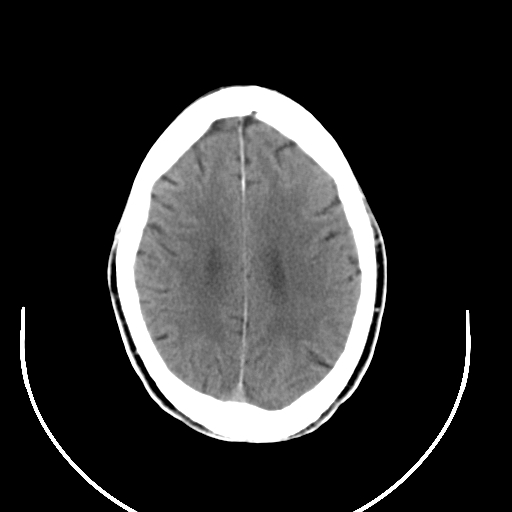

以下是引用拾荒者在2008-7-26 15:36:00的发言:[br]侧脑室内高密度钙化影,未见软组织结构,侧脑室未见增大,考虑良性钙化性改变(钙化型脑膜瘤可能)。